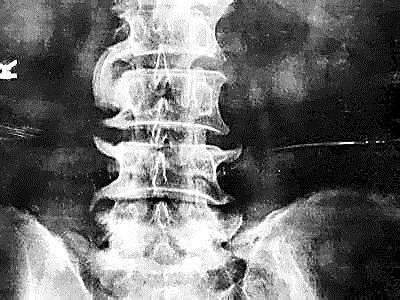

甭管是什么原因引起的,长出来的“骨刺”本质上依旧是骨骼。也就是说,新长出来的骨刺和全身其他部位的骨头,并没有任何成分上的区别。不仅外观上无区别,在片子上无区别,甚至连成分都一样。